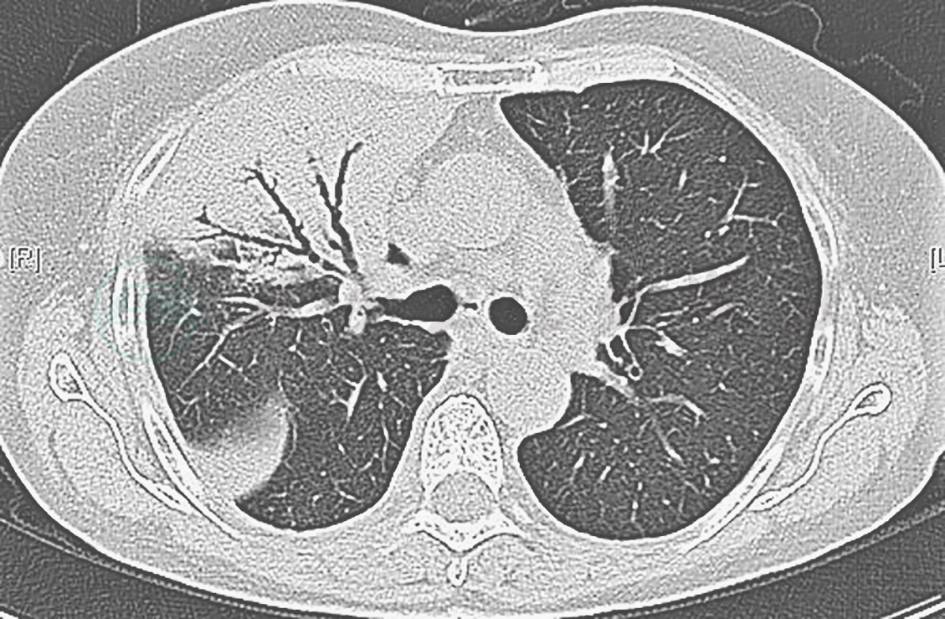

全身血液系统肿瘤肺部浸润:例如,肺黏膜相关淋巴瘤可出现肺部实变影,支气管充气征达远端实变肺野(图7)。该病诊断较困难,也较少发生,主要依据骨髓、淋巴结、肿瘤活检等检查明确诊断。本例患者反复发热,有患该病可能,需进一步检查鉴别。

图7 肺黏膜相关淋巴瘤胸部影像学表现

胸部CT可见双肺中下大片磨玻璃高密度及实变影,并见支气管充气征

(3)成人Still病

患者反复发热、抗感染治疗效果欠佳,需注意与成人Still病肺内表现相鉴别。该病的主要表现为间质性肺炎、浸润性肺炎和胸膜炎(图8),多伴有关节疼痛或肿胀、皮疹,可累及多个系统。其诊断需在排除器质性疾病后方能做出。对于本病例,目前还有待完善相关检查,以排除之。

图8 成人Still病胸部影像学表现

胸部CT可见双上肺间质性改变、实变和胸腔积液,其中右侧更为明显

(4)急性纤维素性渗出性肺炎(AFOP)

亚急性起病,临床和影像学表现(图9)无特异性,诊断主要依赖于肺组织活检。

图9 急性纤维素性渗出性肺炎胸部影像学表现

胸部CT可见以左下肺受累为主的实变影